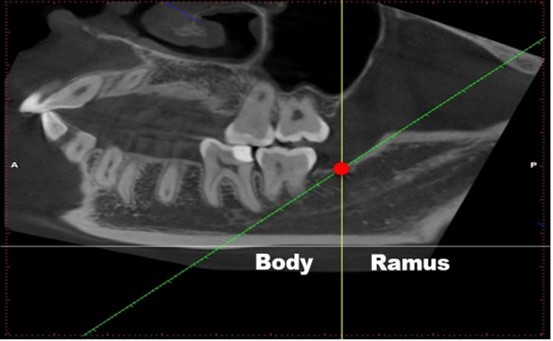

The second reading process was somewhat different: the researchers adjusted the sagittal images to make the lower edge of the mandible parallel to ground, then: (1) a horizontal line was made parallel to the lower edge of the mandible (Figure 1, grey line); (2) a tangent line was made along with the front edge of the mandibular ramus (Figure 1, green line), which intersects with the upper edge of the mandibular body (Figure 1, red circle); (3) a line across the intersection was made vertical to the line in (1) (Figure 1, yellow line). We defined the following: the bifurcation that appears in front of this vertical line (yellow line) is classified into mandibular body area, whereas the bifurcation that appears behind it is the mandibular ramus area (Figure 1). The classification of each type depends on the starting point of the bifurcation. Details are provided in Table 1.

Figure 1.Image-reading position. (1) a horizontal line was made parallel to the lower edge of the mandible (grey line); (2) a tangent line of the front edge of the mandibular ramus (green line), which intersects with the upper edge of the mandibular body (Fig. 1, red circle); (3) a line across the intersection was made vertical to the line in (1) (Fig. 1, yellow line). We defined the following: the bifurcation that appears in front of this vertical line (yellow line) is classified into mandibular body area, whereas the bifurcation that appears behind it is the mandibular ramus area (Fig. 1).